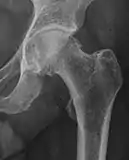

X-ray

Projectional radiography ("X-ray")is often considered first line for FAI.[10] Anterior-posterior pelvis and a lateral image of the hip in question should be attained.[10] A 45-degree Dunn view is also recommended.[10][19]

Three types of FAI are recognized (see title image). The first involves an excess of bone along the upper surface of the femoral head, known as a cam deformity (abbreviation for camshaft, which the shape of the femoral head and neck resembles). The second is due to an excess of growth of the upper lip of the acetabular cup and is known as a 'pincer' deformity. The third is a combination of the two, generally referred to as 'mixed.' The most common type seen, approximately 70% of the time, is the mixed type.[13] A complicating issue is that some of the radiographic findings of FAI have also been described in asymptomatic subjects.[14]